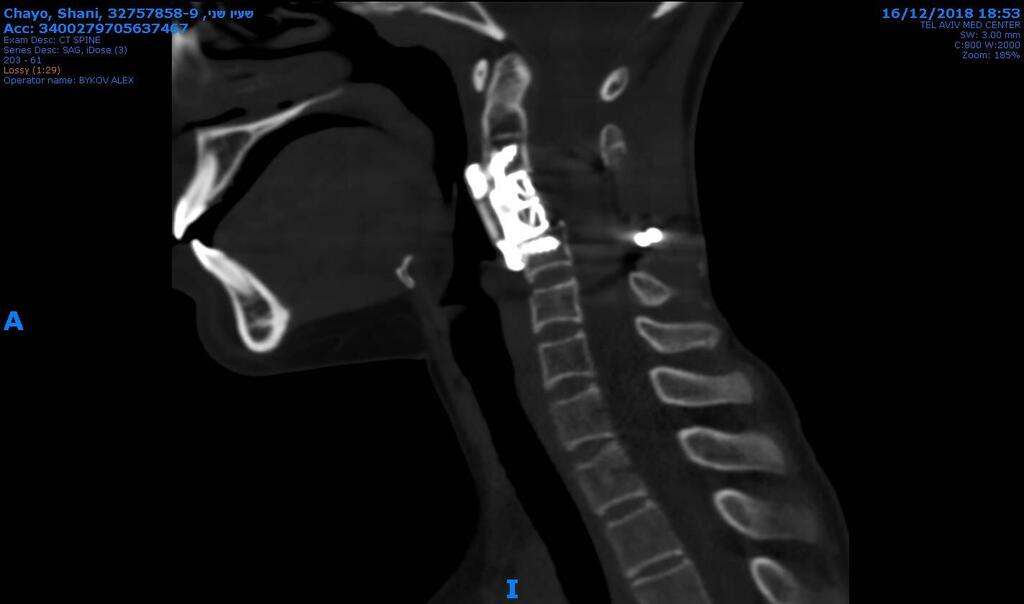

Ewing sarcoma often presents with pain at the tumor site. In Shani’s case, it had developed in the C3 cervical vertebra, close to the skull. “Its position made it uniquely challenging, requiring high technical skill, experience, and patience,” said Lidar.

The surgery was performed in two stages: first with Shani lying on her stomach, then on her back. “With spinal cancer surgery, it’s critical to remove the tumor in one piece. But how can you do that when the spinal cord runs through the middle and even the smallest injury risks paralysis?” Lidar said.

Prof. Zvi LidarPhoto: Yuval ChenPreparations alone took three hours. The team began by making an incision at the back of her neck. “I released the affected vertebra, the surrounding bones, and the arteries to the brain. That freed the spinal cord and created a safe surgical space. We stabilized the area, which took seven hours. Then we turned her over,” Lidar explained.

Through an incision in the front of her throat, the team shifted aside her windpipe and esophagus to reach the diseased vertebra. Working carefully above and below it, they fully separated it before removing it whole. In its place, they implanted a custom-made replacement vertebra designed specifically for Shani.